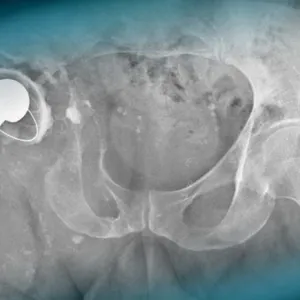

A 57-year-old man with a history of hypertension and a right hip replacement in 1993 presents with worsening right hip pain over 10 years. He uses one cane, has a 3 cm leg length discrepancy, and a soft mass in the groin. What are your diagnostic hypotheses?